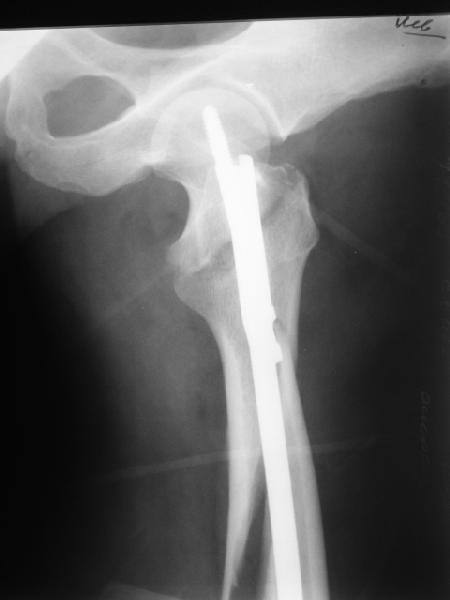

В диагноз пишем... Потом же как-то анализировать надо. Что-то никто не откликнулся на этот вопрос из англоязычных коллег. Все-таки - как такой перелом надо классифицировать? А если шейка бедра + диафиз? Завтра покажу такой случай.

Реконструкционный гвоздь.

Да, сейчас это и у нас самый напрашивающийся выбор. Сделали гвоздем ChM, картинки в приложении.

У молодых реконструкционный гвоздь самое то. При остеопорозе надо что-то помассивнее.